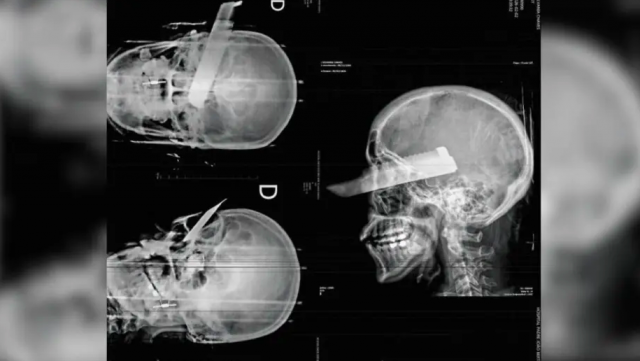

Uma mulher sofreu uma tentativa de feminicídio na manhã desta segunda-feira (2) em São Carlos, no Oeste de Santa Catarina, ao ser atacada pelo companheiro dentro da residência do casal. O agressor desferiu um golpe de faca no rosto da vítima, atingindo o olho direito, mas o crime não se consumou, segundo a polícia, graças ao pronto atendimento médico.